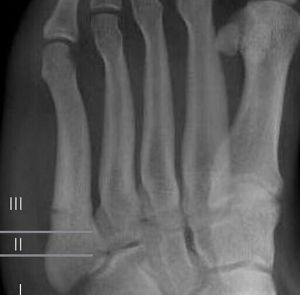

而更多學者將此部分骨折分為3區不同性質的骨折:

(1)粗隆部的撕脫骨折;

(2)乾骺端和骨幹連線部骨折;

(3)近端骨幹的應力性骨折。